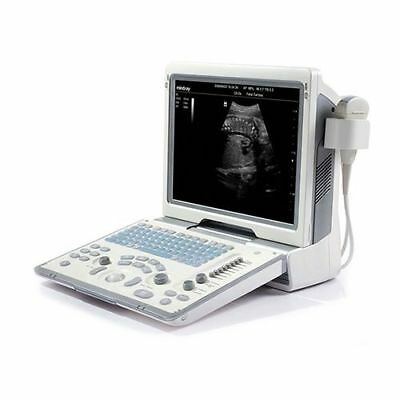

DIAGNOSTIC ULTRASOUND MACHINES FOR SALE

Mindray DP-30 Ultrasound Diagnostic Imaging Device

Sale price$ 17,549.99

Save $ 400.00